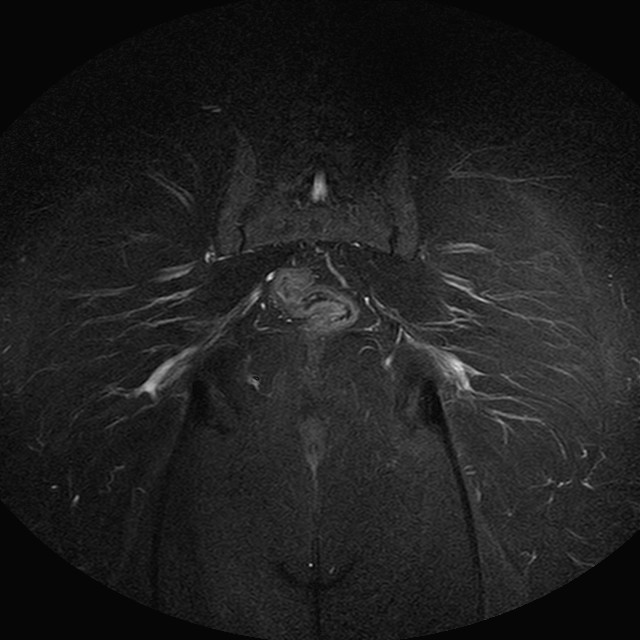

Esami: RMN BACINO

eSTIR

Evidenti e simmetriche alterazioni osteofitosiche in regione coxo femorale con riduzione delle rime articolari. Degenerazione completa del cercine glenoideo. Non attuali segni di versamento articolare. Non segni di edema osseo che escludono attuale algodistrofia od osteonecrosi. Lieve e simmetrica riduzione del trofismo della muscolatura glutea.